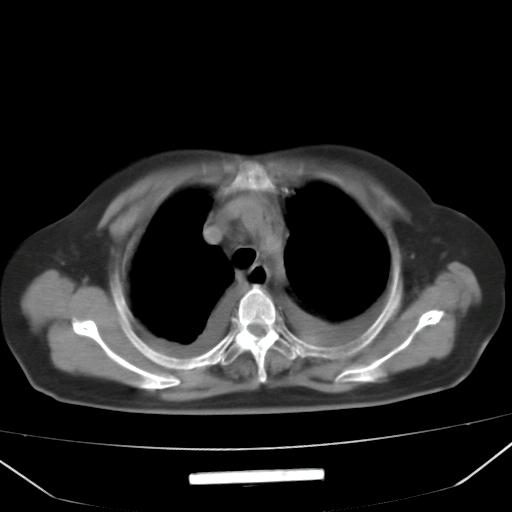

以下是引用liuyue在2008-4-19 22:25:00的发言:[br]先考虑:1.心衰伴肺水肿、双侧胸腔积液、叶间积液、双下肺不完全性肺不张; [br] 2.冠状动脉粥样硬化。

以下是引用lijuanln在2008-4-19 23:05:00的发言:[br]两侧胸腔积液,肺水肿[br]心包积液[br]提示心衰

以下是引用jiangjing在2008-4-20 10:43:00的发言:[br]结合病史支持 冠心病[冠状动脉钙化],心功能不全,肺淤血、肺水肿,双侧胸腔与斜裂积液